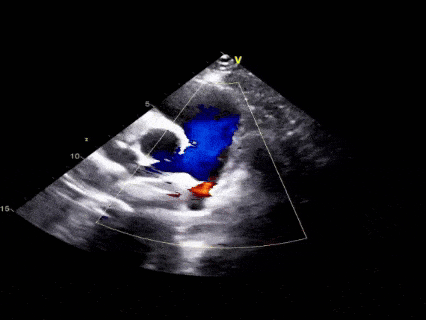

术前超声再次确认

动脉水平可见明显彩色血流